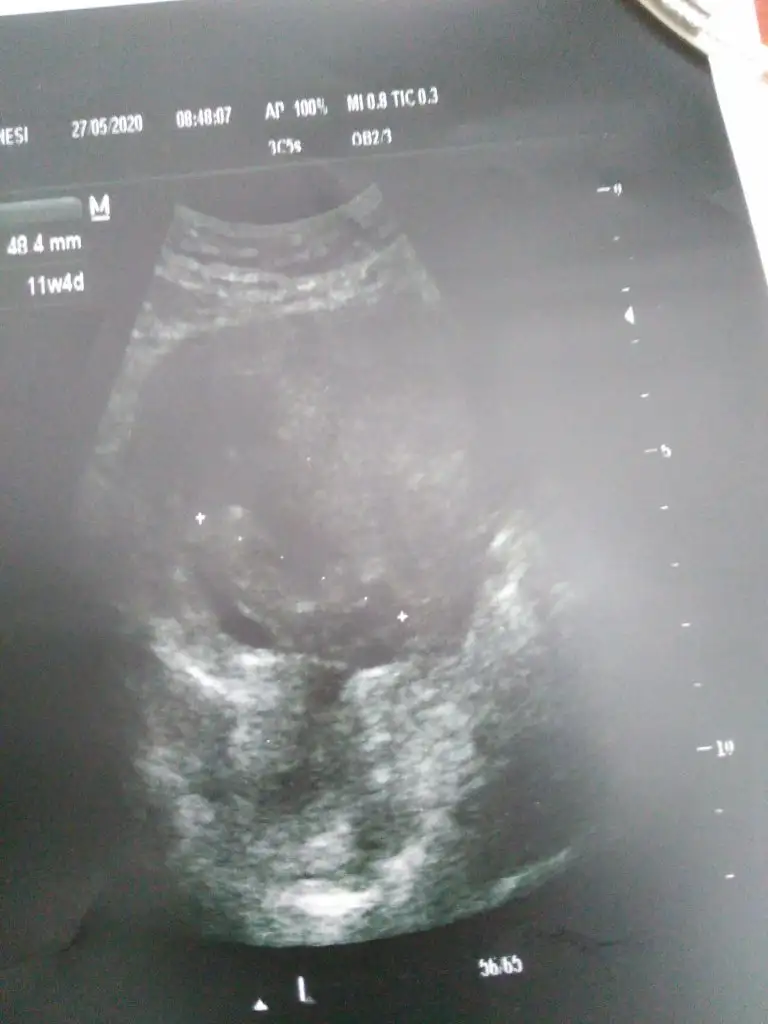

Hanımlar biz doktordan geldik 11+4 uz iyiyiz cok şükür :) cok belli olmuyor ama cinsiyet tahmini alabilirim.. Bu arada bulunduğum yerde 2 li test yokmus tamamen insiyatif dedi doktorum merkeze de uzağım yaptirmayacagim 3 lumu 4 lumu ne o varmış onu yapacakmış herhalde.. 20 gun sonra tekrar gel dedi. :)